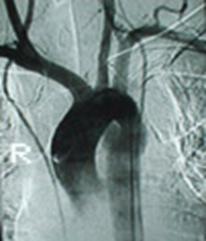

Lipsa vascularizatiei rinichiului stang Angiograma

Lipsa vascularizatiei rinichiului stang